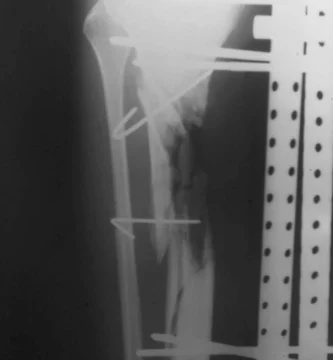

Imágenes para Evaluar Fracturas de Tibia